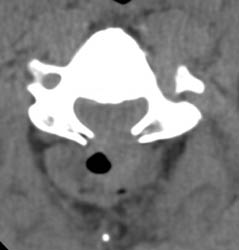

63 y.o. male with severe spinal stenosis and associate myelopathy in both hands and feet. Patient underwent laminectomy from C2-C7. 1 day after initial operation patient with severe numbness to left arm. Then, patient became unable to move either leg within 2 hours after that initial complaint. A Stat non-contrast CT was ordered.

Axial CT demonstrates laminectomy defect at the level shown. A hyperdense fluid collection with some air bubbles  is identified consistent with an epidural hematoma, extending from the C2-3 level to C7-T1 (not entirely shown).